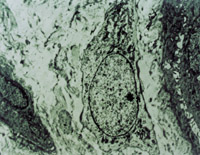

É˺ó12h¼¹ØïÈëÔº£¬²é³­Ë«ÏÂ֫Ϊdz¢ó¶ÈÉÕÉË¡£´´Ãæ±íƤÒÑ»µËÀ°þÍÑ£¬ÕæÆ¤²ã±äÐÔ»µËÀ³ÊÀ¯»ÆÉ«ºÍÀ¯°×É«Ïà¼ä£¨Í¼5-3-1£©¡£È¡²¿ÃÅ×éÖ¯×ö²¡ÀíÇÐÆ¬²é³­£¬ÏÔʾÉÏÆ¤×é֯ȫ²ã»µËÀ£¬ÕæÆ¤²ã½ºÔ­ÏËά±äÐÔ£¬½á¹¹´íÂÒ£¬Î¢Ñ­»·ðöÖÍ£¨Í¼5-3-2£©¡£

5-3-1 Àîij Å® 20Ë꣬ÆûÓÍÉÕÉË35%TBSA £¨Éî¢ò¡ãÉîÐÍ15%£¬Ç³¢ó¡ã20%£©

5-3-2 ÉÏÆ¤×é֯ȫ²ã»µËÀ£¬½ºÔ­ÏËά±äÐÔ£¬Î¢Ñ­»·ðöÖÍ HE¡Á20